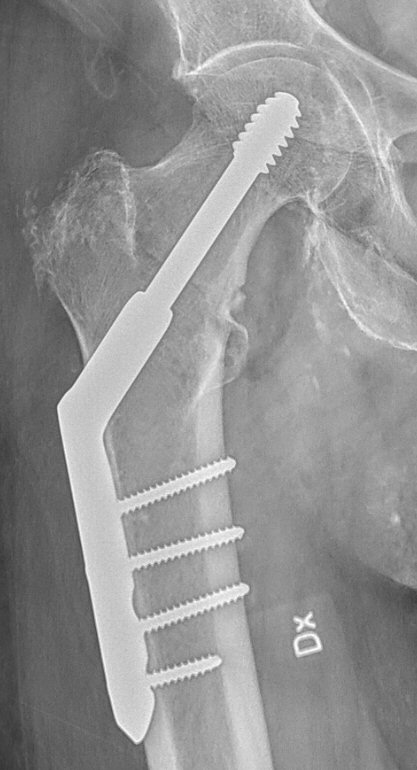

Operation: DHS-platta

DHS = Dynamic Hip Screw

- Kan användas vid många kollumfrakturer, pertrokantära och subtrokantära femurfrakturer.

- Används i praktiken mest vid basocervikala och stabila pertrokantära femurfrakturer.

- Det finns olika plattor med olika antal skruvhål, med eller utan LCP, med olika vinklar, med eller utan stabiliserande trokanterplatta och med glidskruv eller glidblad. Ofta väljs 4-hålsplatta utan LCP, utan trokanterplatta och med glidskruv.

- För in DHS-plattan i hålet över glidskruven. Banka lätt med pusher så plattan ligger helt mot benet. En del föredrar att skruva ut glidskruven en aning, plattan ligger då lite snett i såret, men det kan vara lättare att få den på plats och sedan skruva in glidskruven igen.